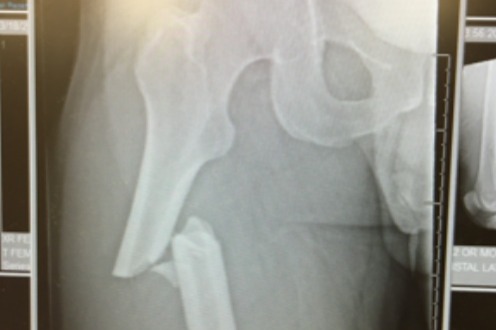

Alex broke his right femur, shattered his left pelvis, and cracked two vertebrae above his tailbone after spinning out into the forest at high speed under the Tombstone lift at Park City Mountain Resort while trying to avoid a collision with another skier. As part of the rescue, the first responders had to cut down two trees that he was wedged between. Fortunately, he was alive! But his injuries were severe and he was rushed to the hospital in an ambulance, preparing for emergency surgery the next morning.

· March 18th, 2021 – Alex was in a ski accident by the Tombstone lift at The Canyons side of Park City Mountain. A small kid popped out from behind a slow sign as Alex was approaching. In order to avoid a collision, Alex made a quick maneuver, caught a ski edge and tumbled into some trees. Ski patrol was there within minutes, brought him off the mountain, and an ambulance rushed him to the University of Utah hospital. Imaging revealed Alex broke his right femur and left pelvis from the impact (several weeks later they confirmed that Alex also cracked to vertebrae above his tailbone).

· March 19th, 2021 – Alex had an 8-hour ortho surgery to repair his femur and pelvis. I don’t know the quantity, but a rod and a gazillion screws were placed in the femur and several plates, screws and pins to repair the pelvis. The surgery was successful and we were anticipating to be discharged from the hospital in 2 – 3 days, with 2 weeks of no weight bearing on the right leg and 3 months of no weight bearing on the left leg. Alex would require a wheelchair.